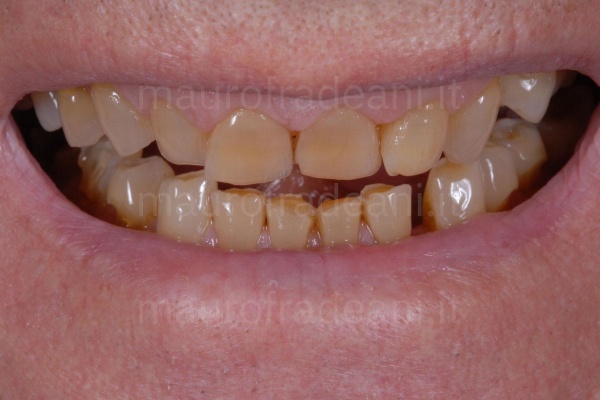

1/4: The patient presents a particularly compromised situation: considerable dental wear, multiple tooth decay and lack of teeth.

2/4: Intraoral view: the patient needs a complete rehabilitation of both arches.